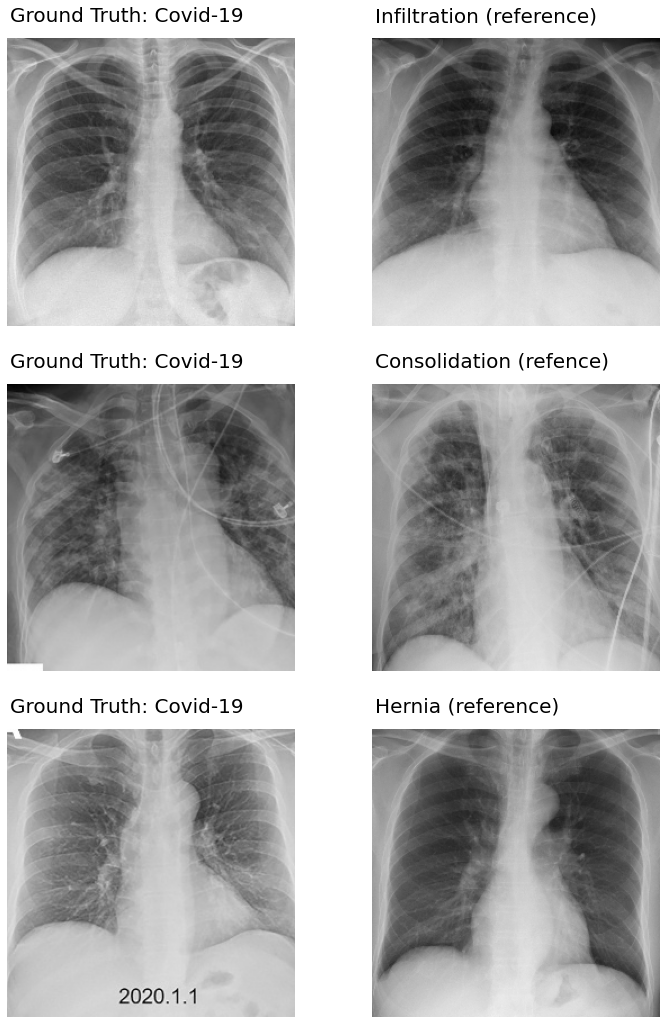

Next in Fig. 6 we display a few COVID-19 cases which are incorrectly classified by the proposed method. The first column depicts the COVID-19 images which are misclassified. The first image (in the top-left panel) is misclassified as Infiltration.

The image in the second panel of row one displays the training image from the Infiltration class that has the highest similarity with the COVID-19 image. Inspection of these two images reveals that both have similar opacification in the lung areas.

The images in the first column of second and third rows are the other two COVID-19 instances which are misclassified as Consolidation and Hernia, respectively. The second image in row two is the training image from the consolidation training set having the highest similarity with the COVID-19 image. Comparison of the first and second images in the second row reveals that both have consolidations on the lungs towards the center of the images, which probably is the cause of misclassification.